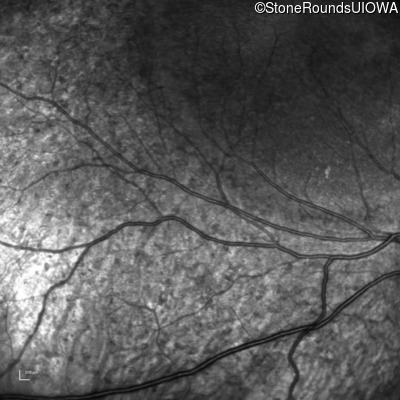

Infrared Fundus Photograph - Right - 20/25

Exemplar